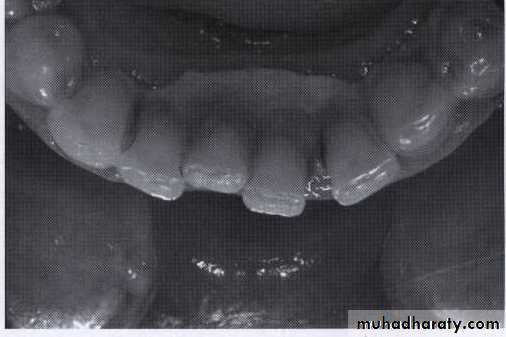

Supragingival calculus

It is yellow-white in colour ,located along gingival margins.

Large amount located at buccal aspect of upper 6 & lingual aspect of lower ant.teeth (next to stenson, warton & bartholin ducts).